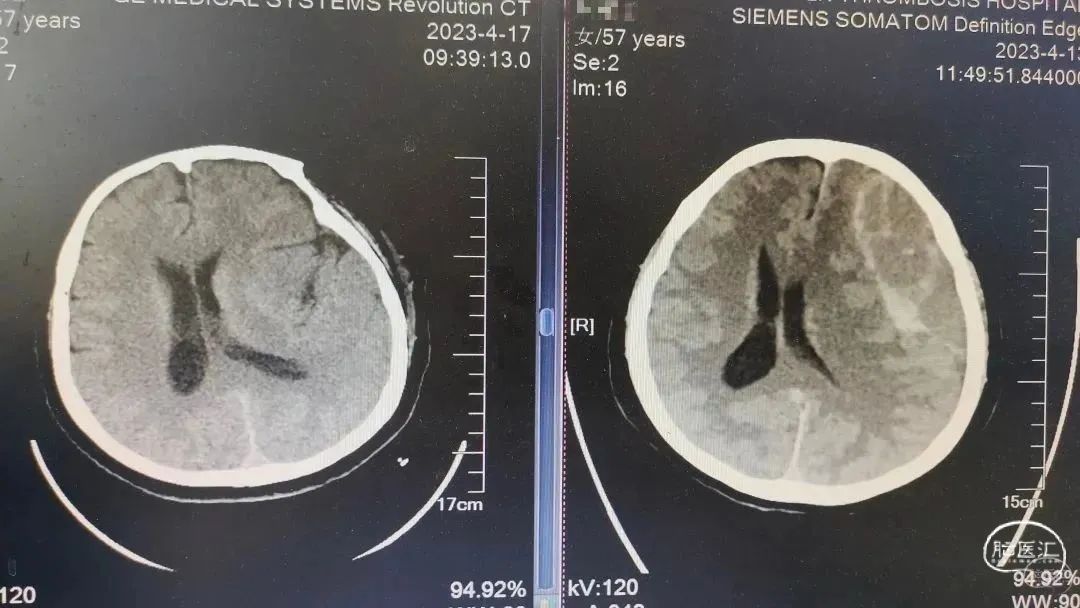

术前CT

术前术后对比